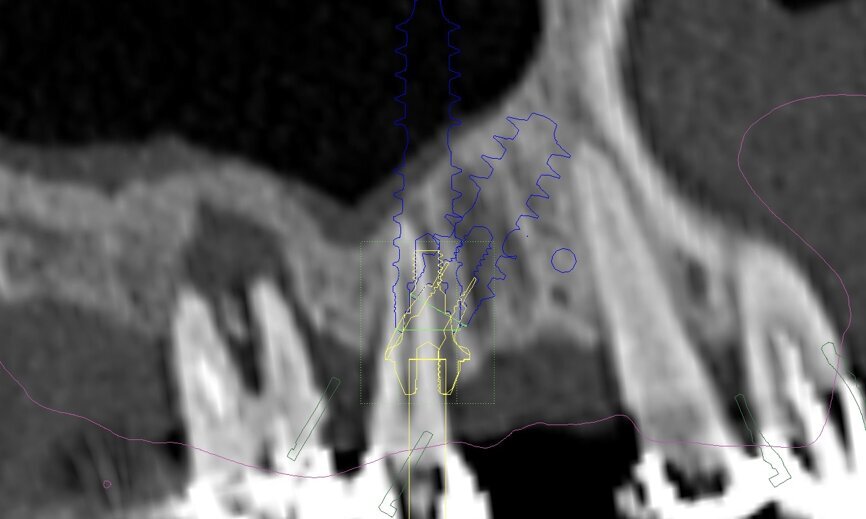

An intra-oral scan was taken to record the patient’s current oral situation, and the resulting STL file and the DSD fil (2D smile design image) were used to create the future prosthetic design with software for the laboratory (Figs. 3–6). The 3D radiographic DICOM data and the prosthetic design project STL file were superimposed in coDiagnostiX (Figs. 7–9) The fixation pin guide, bone reduction guide, surgical guide and bite registration guide were designed with coDiagnostiX (Figs. 10–13) and produced using 3D printing technology.

On the day of surgery, we prepared for the surgical protocol provided by the implant planning software, which guided us on the drilling sequence and the use of the appropriate instruments for the implant bed preparation (Figs. 30a & b). After the fixation pins had been allocated, teeth #17, 16, 15, 13, 12, 22, 23 and 24 were atraumatically extracted and alveolectomy was performed using a bone reduction guide (Figs. 31–36). Four implants (Straumann BLX; regular base; diameter: 4.5 mm; length: 12.0 mm) were placed, two straight implants in the anterior and two titled implants in the posterior. All the implants were stabilised to a torque of 50 Ncm (Figs. 37–43), and the SRAs were placed on top. The SRAs on the posterior implants had an angulation of 30° (diameter: 4.6 mm; gingival height: 3.5 mm) and on the anterior implants an angulation of 17° (diameter: 4.6 mm; gingival height: 3.5 mm; Figs. 44 & 45).